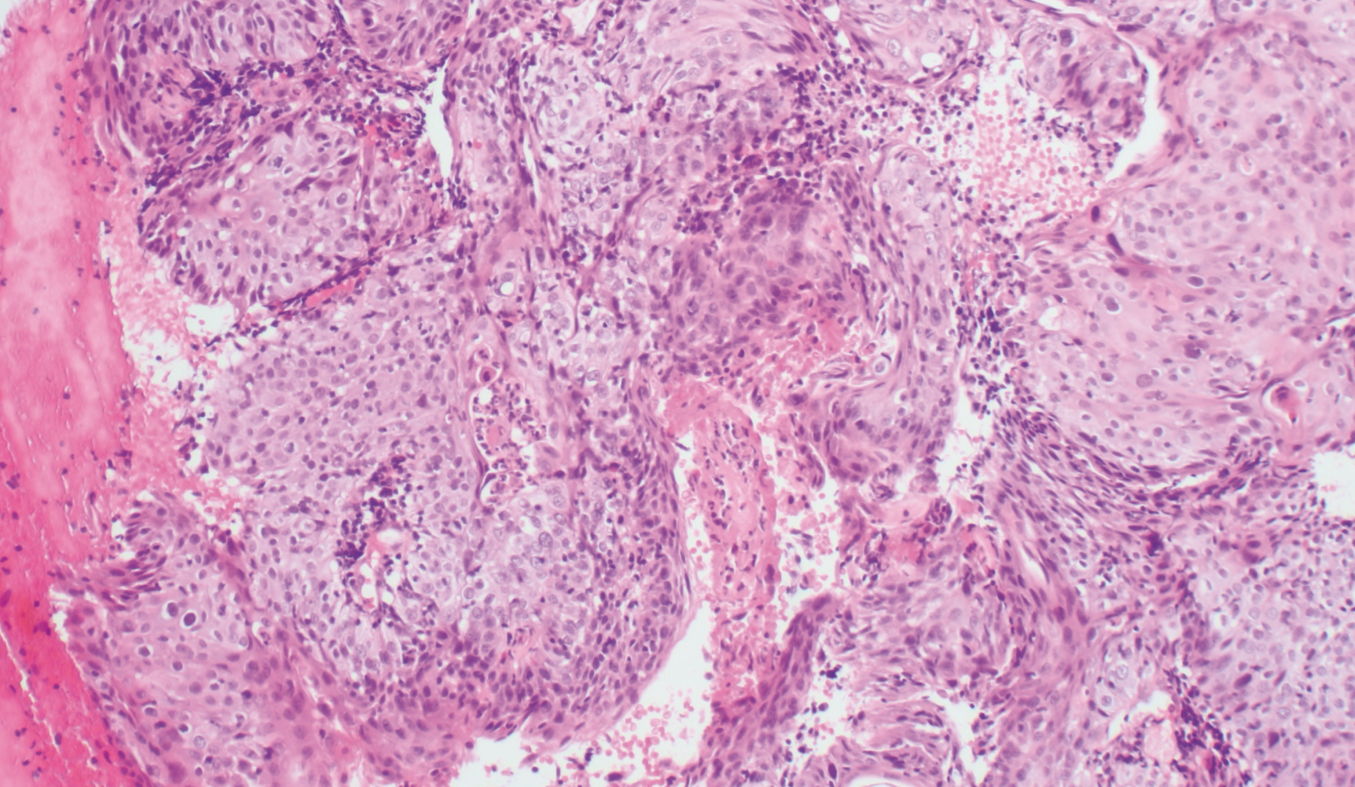

Invasive squamous carcinoma. H&E